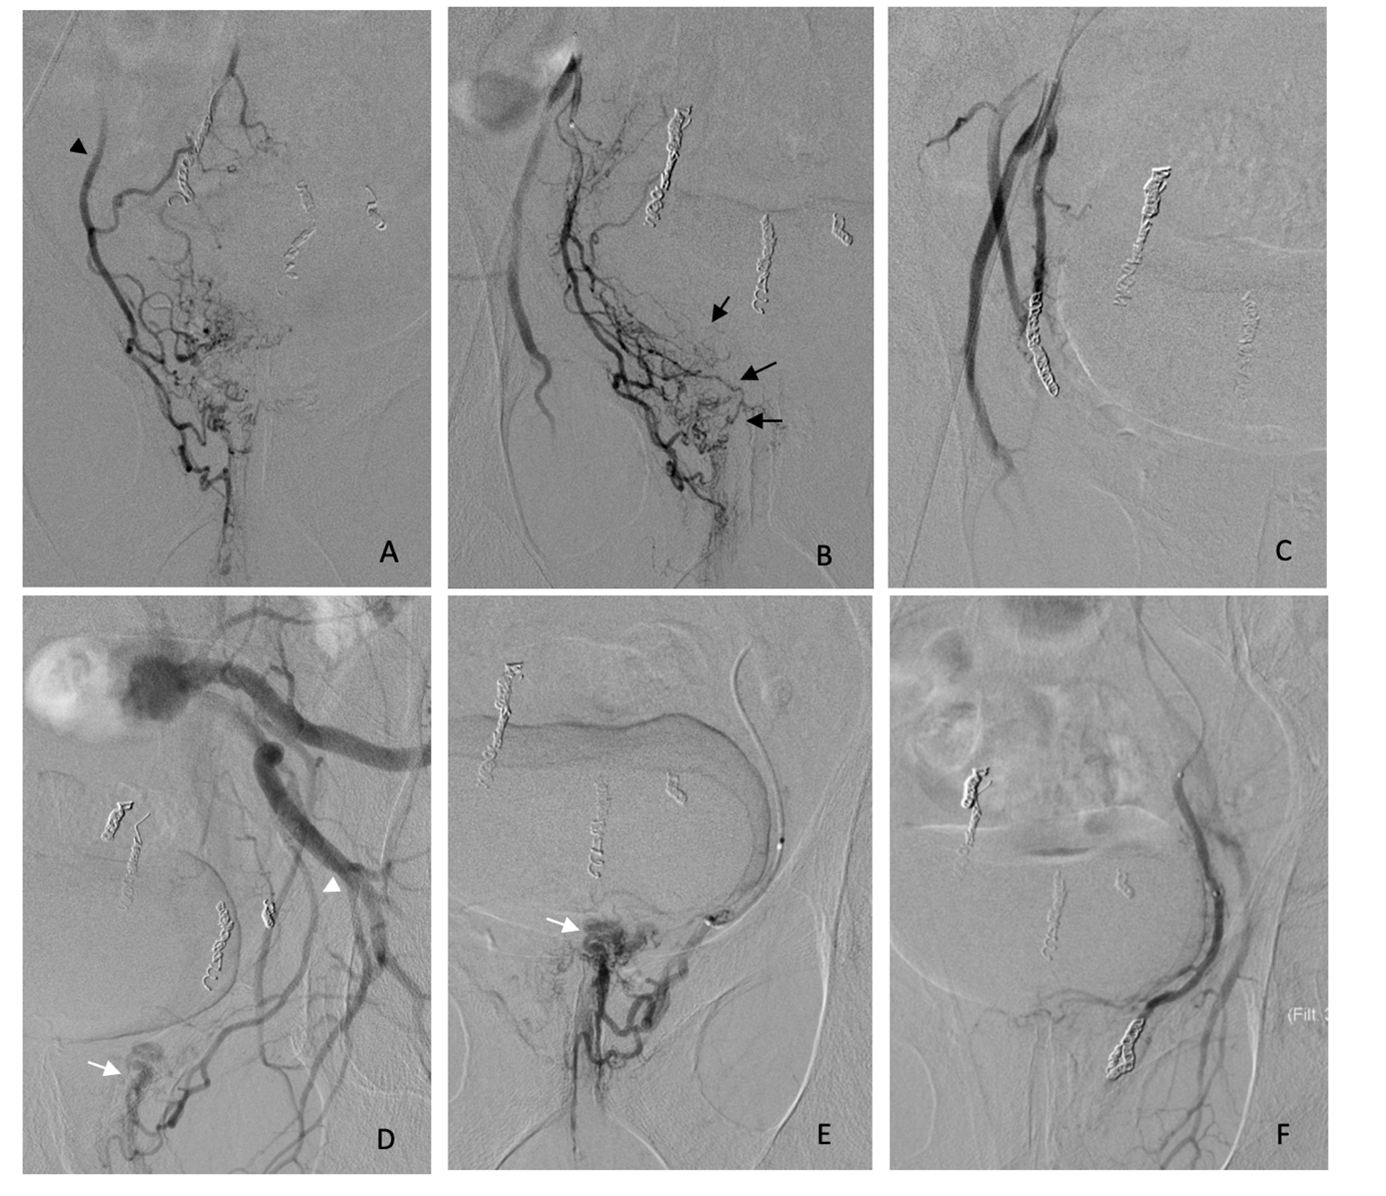

Figure 2. Redo embolization performed 3 months after an initial Emborrhoid procedure for persistent chronic bleeding associated with severe anemia. A) Retrograde opacification of the hypertrophic right MRA (black arrowhead) following SRA injection. D) Anterograde opacification of a markedly enlarged left MRA, not visualized on power injection through the SRA (white arrowhead). B) and E) Selective antegrade catheterization of both the right and left MRAs, with opacification demonstrating intense pseudotumoral enhancement of the right CCR (black arrows) and a large arteriovenous fistula (white arrows). C) and F) Angiographic images demonstrating technical success of embolization of the right and left MRAs using a combination of large microspheres and microcoils. The patient remained free of symptom recurrence after 5 years of follow-up.